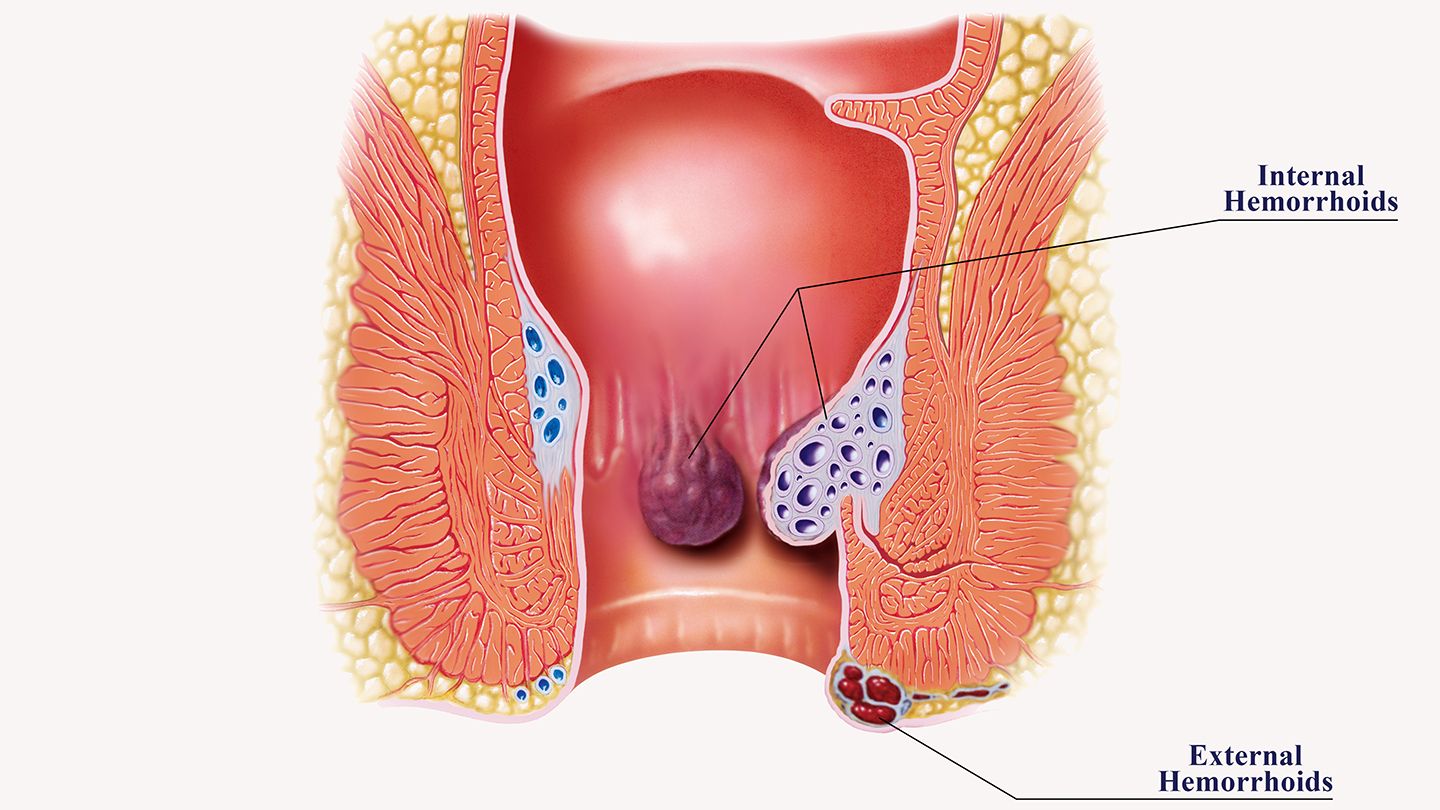

Overview

Package includes:

Days in hospital : 3 to 4 Days (For patient and one attendant)

Days in hotel : 10 Days (For patient and one attendant)

Room type in hospital : Shared

Room type in hotel : Private

Hotel category: Standard

Value added benefits of the Haemorrhoidectomy - Routine:

Overview

Package includes:

Days in hospital : 2 to 3 Days (For patient and one attendant)

Days in hotel : 7 Days (For patient and one attendant)

Room type in hospital : Shared

Room type in hotel : Private

Hotel category: Standard

Value added benefits of the Stapler Haemorrhoidectomy: